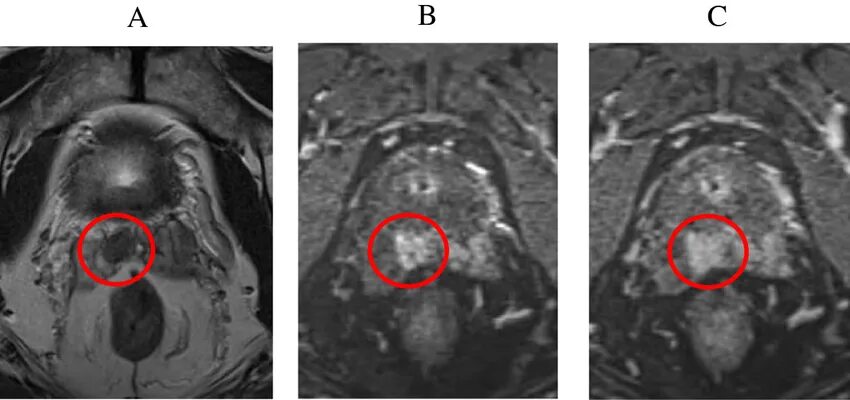

Ммрт